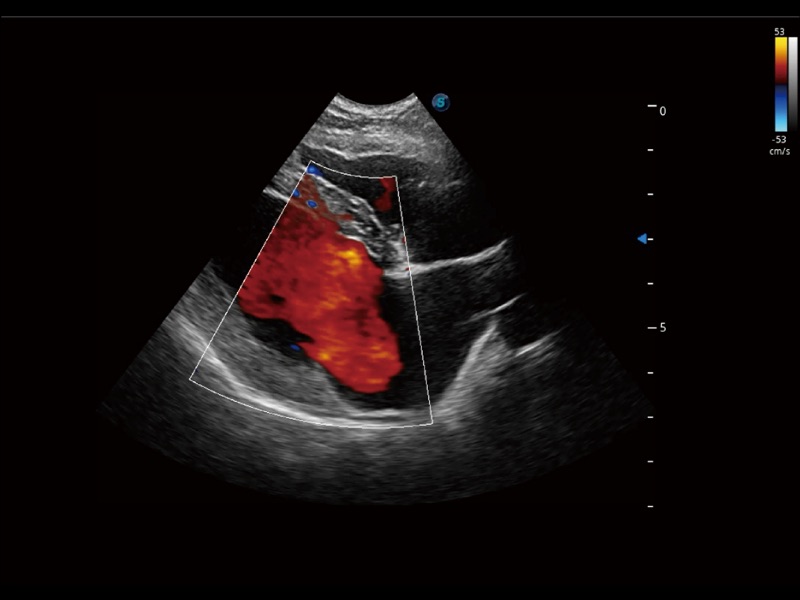

通过创新的 Matrix E自适应滤波器和超长时间域算法,极大提升超低速微细血流的检出能力,同时更精准地滤除软组织和噪声信号,为兽用医生提供以往无法通过常规血流获得的疾病诊断信息。